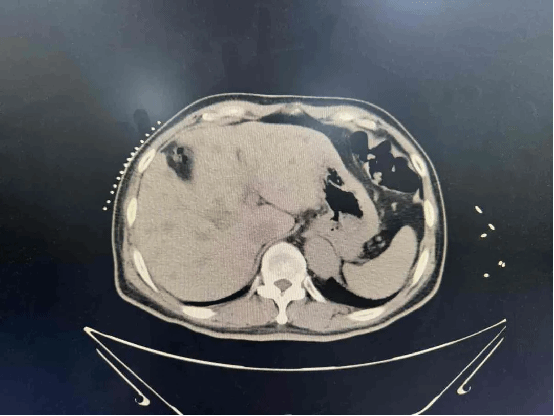

73岁的魏大爷,3月来体重明显减轻,数项肿瘤标志物显著升高,腹部CT发现低密度强化结节,考虑肿瘤性病变,结合既往丙肝病史,高度怀疑肝恶性病变可能。因为高龄,无法耐受手术,我院肿瘤科针对魏大爷这种“高龄、无法耐受手术、小病灶、无远处转移”的情况,经科室专家讨论,决定为其使用一种最适合他情况的新武器——肝占位穿刺术+微波消融术。此微创手术在CT引导下完成,全程无明显痛苦,只需局部麻醉,短短几分钟,肝脏的病灶就被完全“消灭掉”。